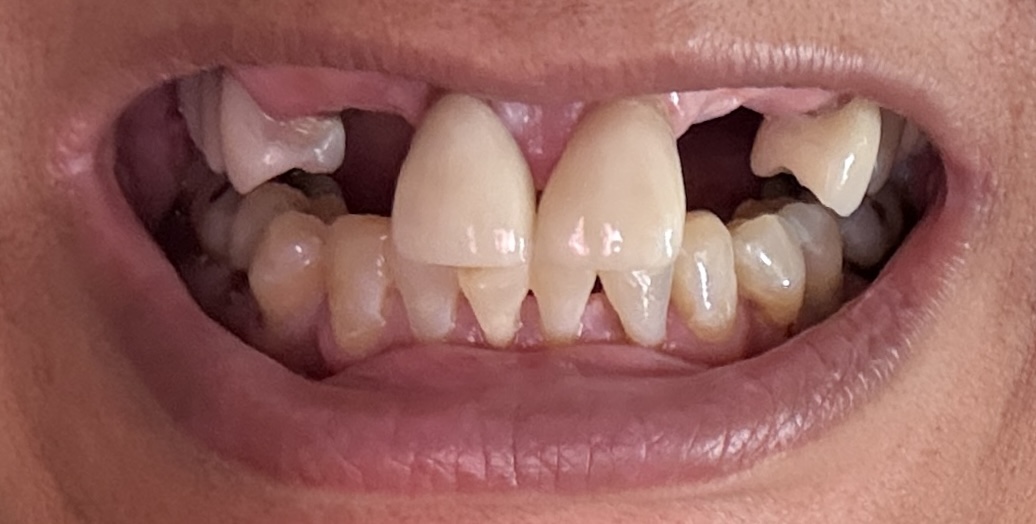

Dental Auction No. 11561: Several extractions and All-on-4 Top and bottom arches

12,13,14 have had root canals in past and now have quite a bit movement. 2-5 have all had root canals in past and now the crowns are breaking down.

Overall information (lower arch)

Overall, all of my gums have receded and most of the bottom teeth are exposed w/ some roots and there are many cavities.